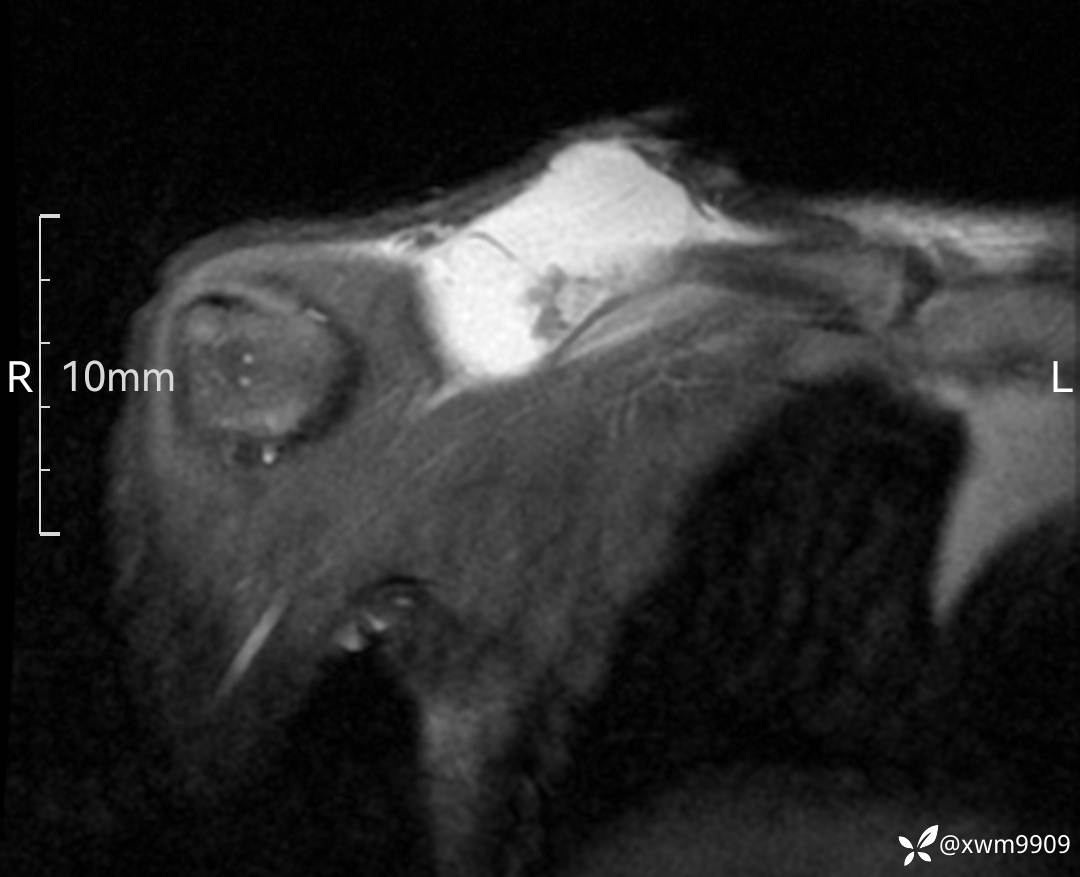

3、查体,右锁下方可及一约5x6Cm肿物,软丶边清丶未见明显发红,肤温不高,压痛明显,不可推动,稍有波动感。其他无特殊。

2、CT、MR肿块内可见液-液平面,常见有哪些疾病。